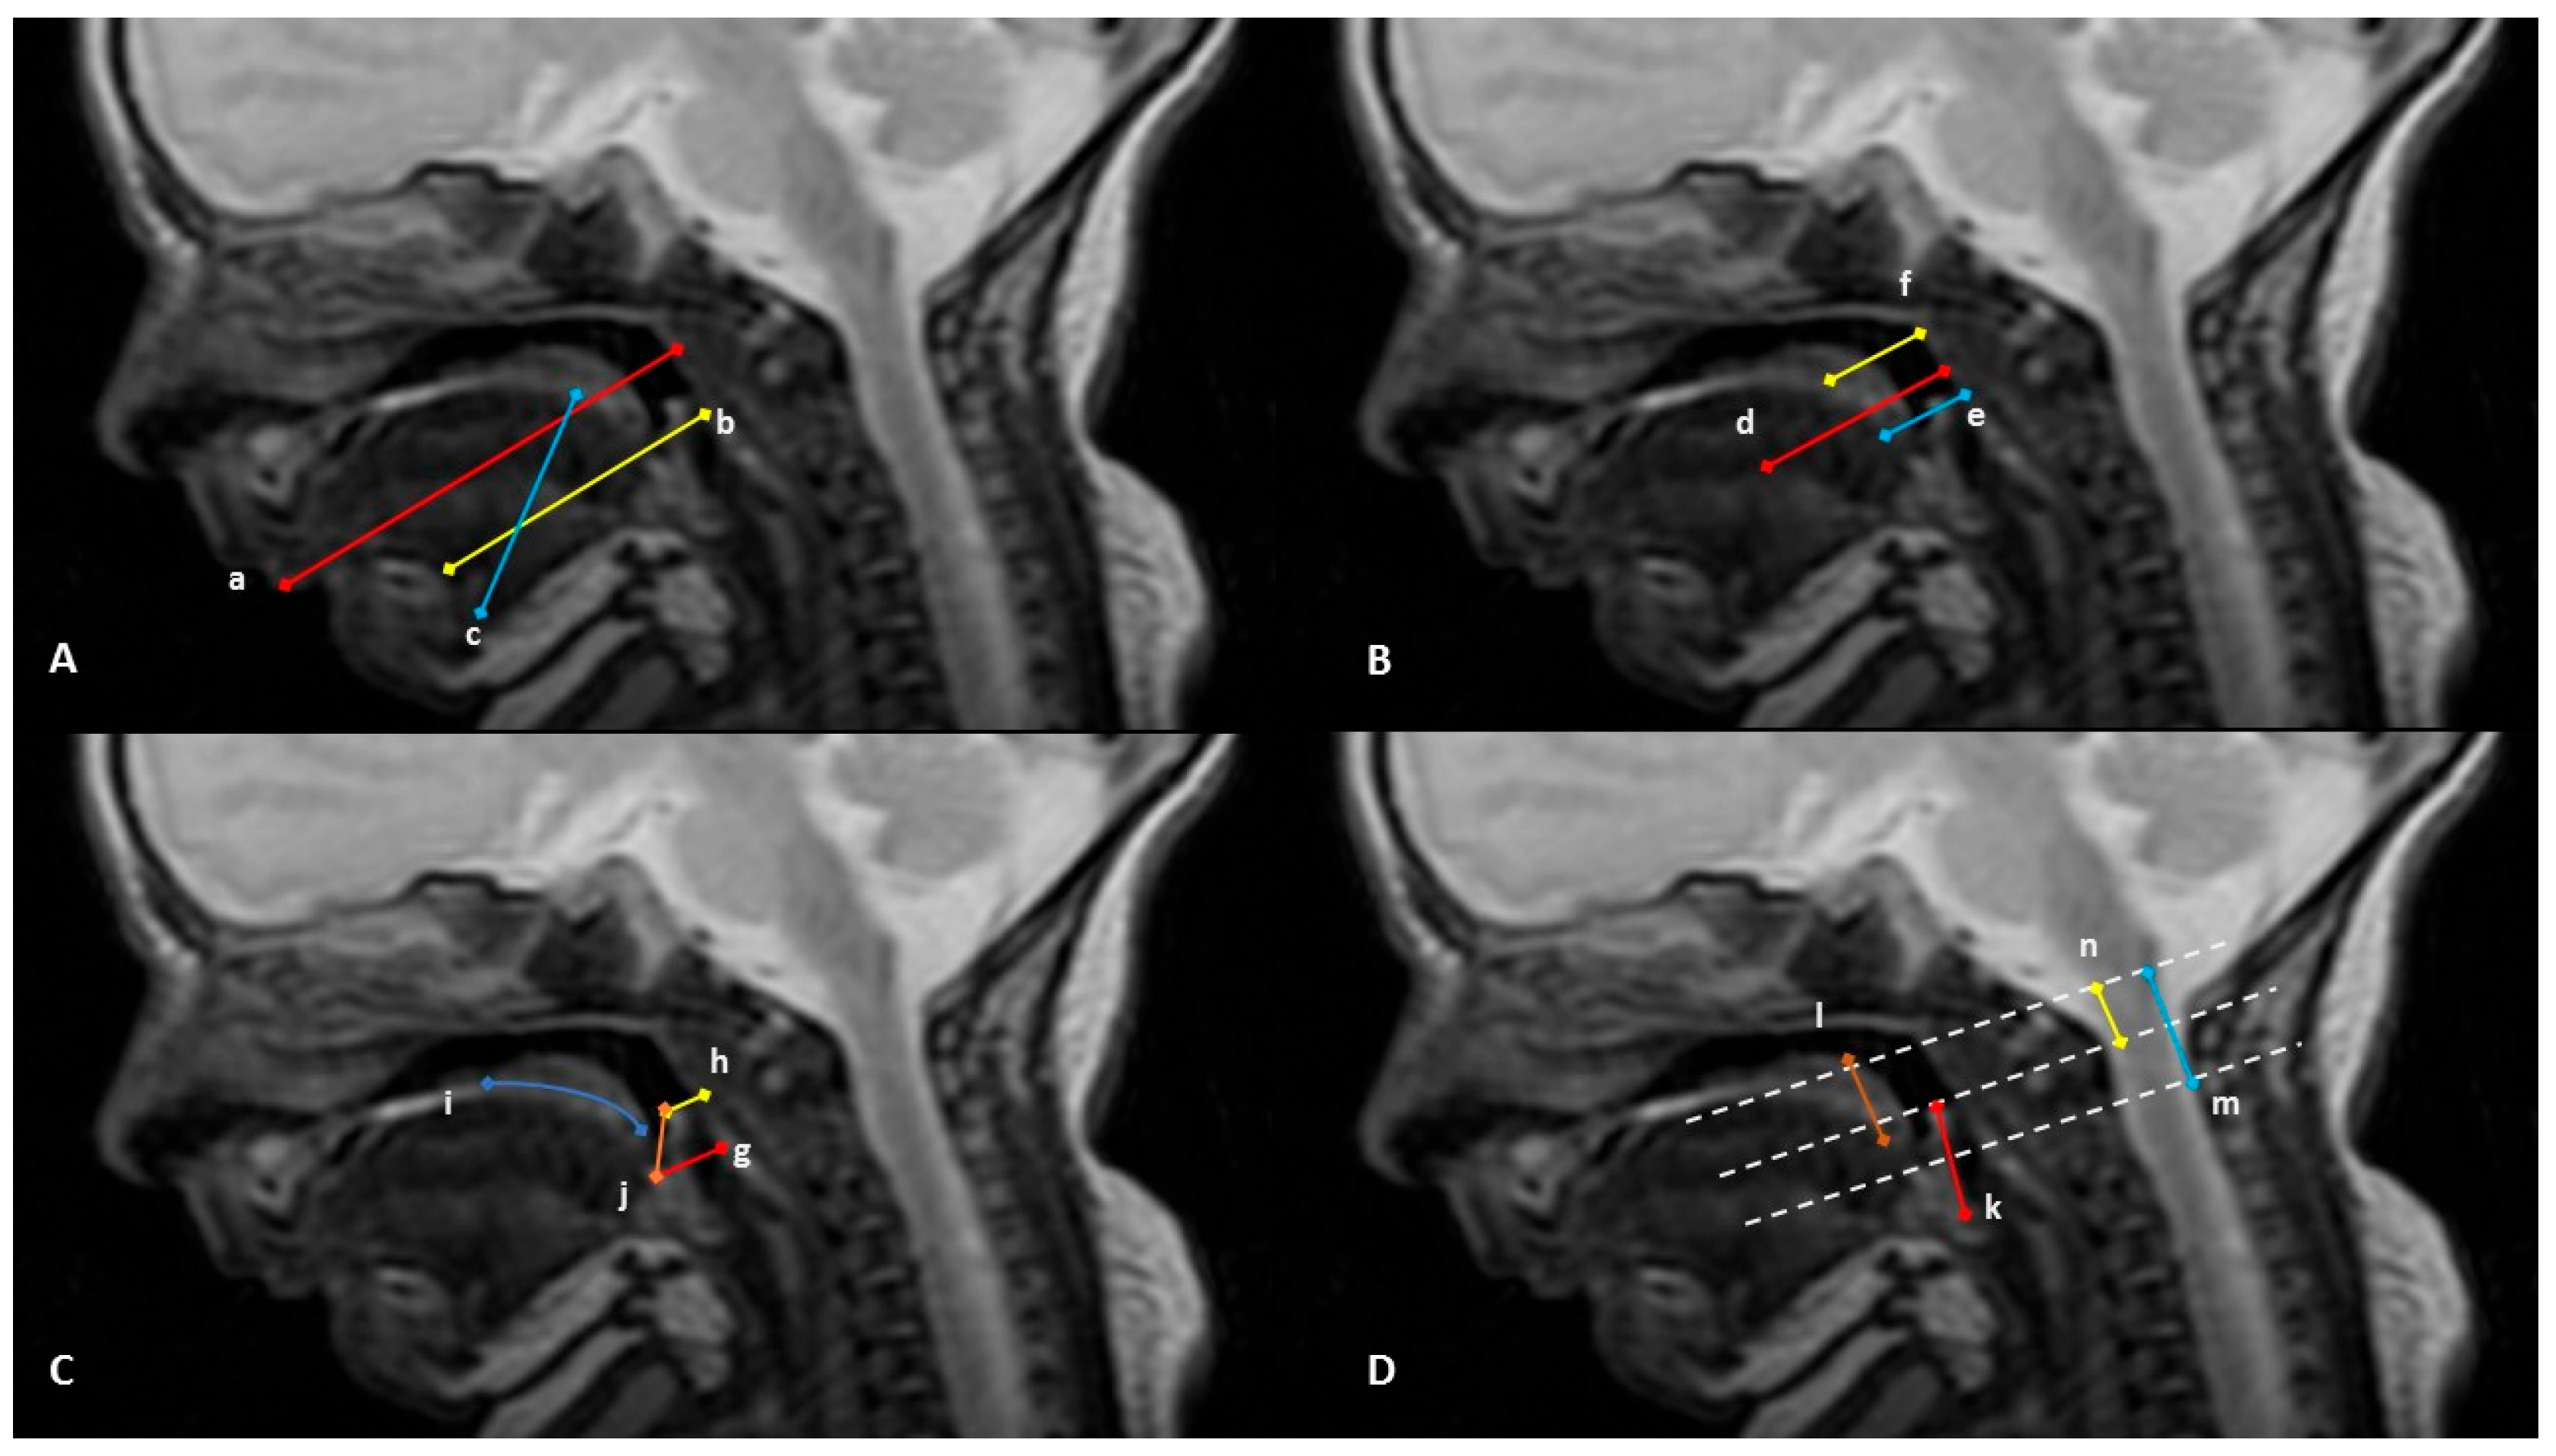

| DISTANCES |

| A. Horizontal distance from the outermost portion of lower lip to the posterior pharyngeal wall |

| B. Horizontal distance from the lower alveolar process to the posterior pharyngeal wall |

| C. Oblique diameter of the tongue |

| D. Horizontal distance from the center of the tongue to posterior pharyngeal wall |

| E. Horizontal distance from the edge of the tongue to posterior pharyngeal wall |

| F. Horizontal distance from the canter of the soft palate to posterior pharyngeal wall |

| G. Horizontal distance from the vallecula to posterior pharyngeal wall |

| H. Horizontal distance from the tip of the epiglottis to the posterior pharyngeal wall |

| I. Curved length of the soft palate |

| J. Distance from the vallecula to the tip of the epiglottis |

| K. Distance from the posterior base of the epiglottis to the tip of the epiglottis |

| L. Height of the soft palate |

| M. Vertical distance from the base of the hard palate to the tip of the epiglottis |

| N. Vertical distance from the base of the hard palate to the vallecula |